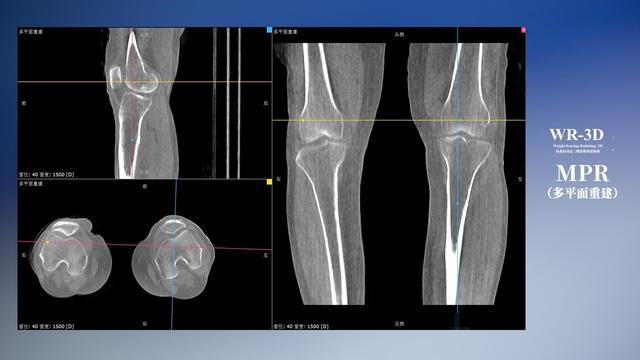

普通平片扫描与WR-3D扫描前后诊断结果对比

与此同时,数字化X线摄影技术相较于CTMRI来说,能快速获取真实、直观、满足临床需要的影像。DR的图像具有图像层次丰富、空间分辨力高、影像边缘锐利清晰、密度分辨力高级细微结构表现出色等特点,针对膝关节解剖结构数字化X线摄影技术应用价值很高,尤其是是对骨小梁与骨皮质的显示非常清楚。在负重位状态下,数字化X线三维摄影扫描与重建,能够更好的呈现受检者关节受力改变的状态。太阳成集团tyc122cc入口科技创新的WR-3D动态三维数字化X线摄影技术,通过数字化X线摄影完成三维扫描并重建三维影像信息,包括MPR多平面重建、MIP重建以及VR绘制。扫描时间短,剂量相较于CT设备大幅缩减,同时成本更低,在临床诊断以及医疗方案制定中具有极大的价值意义。相较于普通平片下的负重位扫描,负重位动态三维扫描摄影技术能够避免二维状态下的组织结构重叠、密度分辨率不足、组织解剖结构难以分辨等问题,WR-3D支持多角度的动态三维摄影观察,能全面的呈现被检查部位在多个角度下三维影像信息,极大的减少了二维负重位检查的漏诊率。

太阳成集团tyc122cc入口科技WR-3D负重位动态三维摄影技术